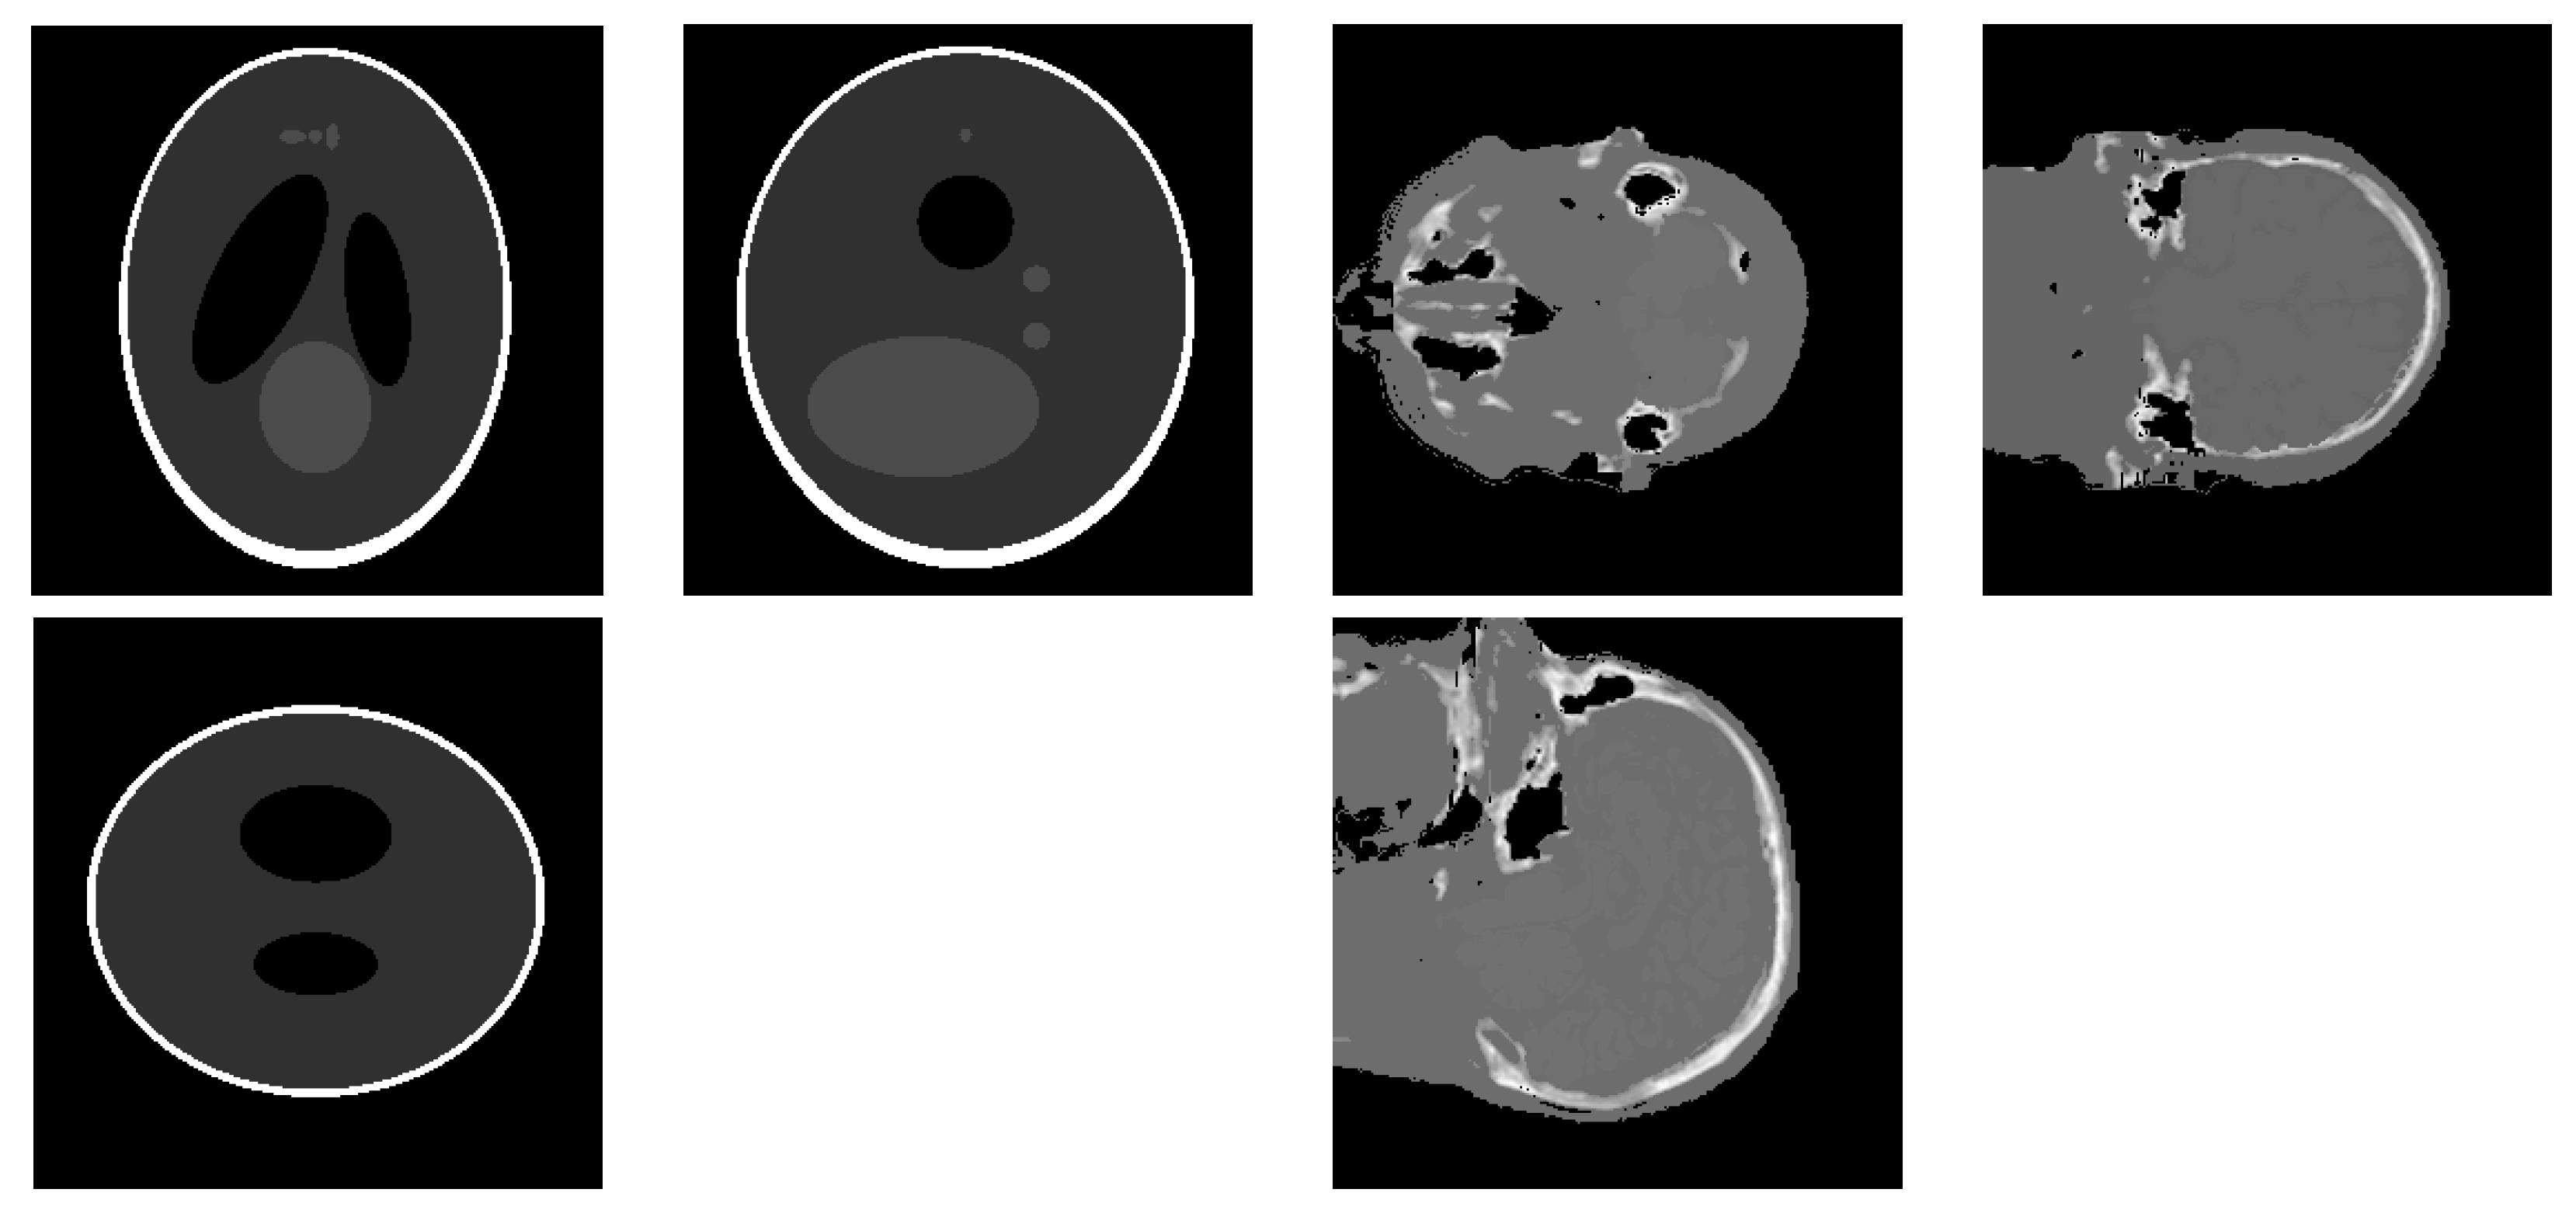

3.2. Simulation Results with a Limited Number of Projections

3.3. Simulation Results with a Limited Angle of Projections

3.4. Simulation with a Different Forward Model